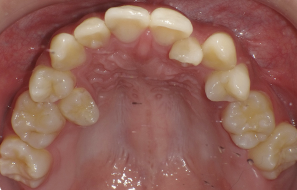

本院為40年 口腔外科專業診所,主攻”安全、無痛”、專拔高風險(牙根與神經交錯或緊貼)、高難度、深度阻生智齒手術。

☆本院特別巨資增設 ”千萬級3D AI透視電腦斷層”,並配合“成骨膠原蛋白”施作 (上述兩項目前健保無給付),讓您遠離神經傷害、口鼻竇(炎)相通...等併發症,除健保之外,難免會有避免併發症風險的自費項目,網路上經常會有看到智齒拔完後唇麻、舌麻、口鼻竇相通等併發症,在本院嚴格自我要求下,此類併發症在本院幾乎趨近於零。